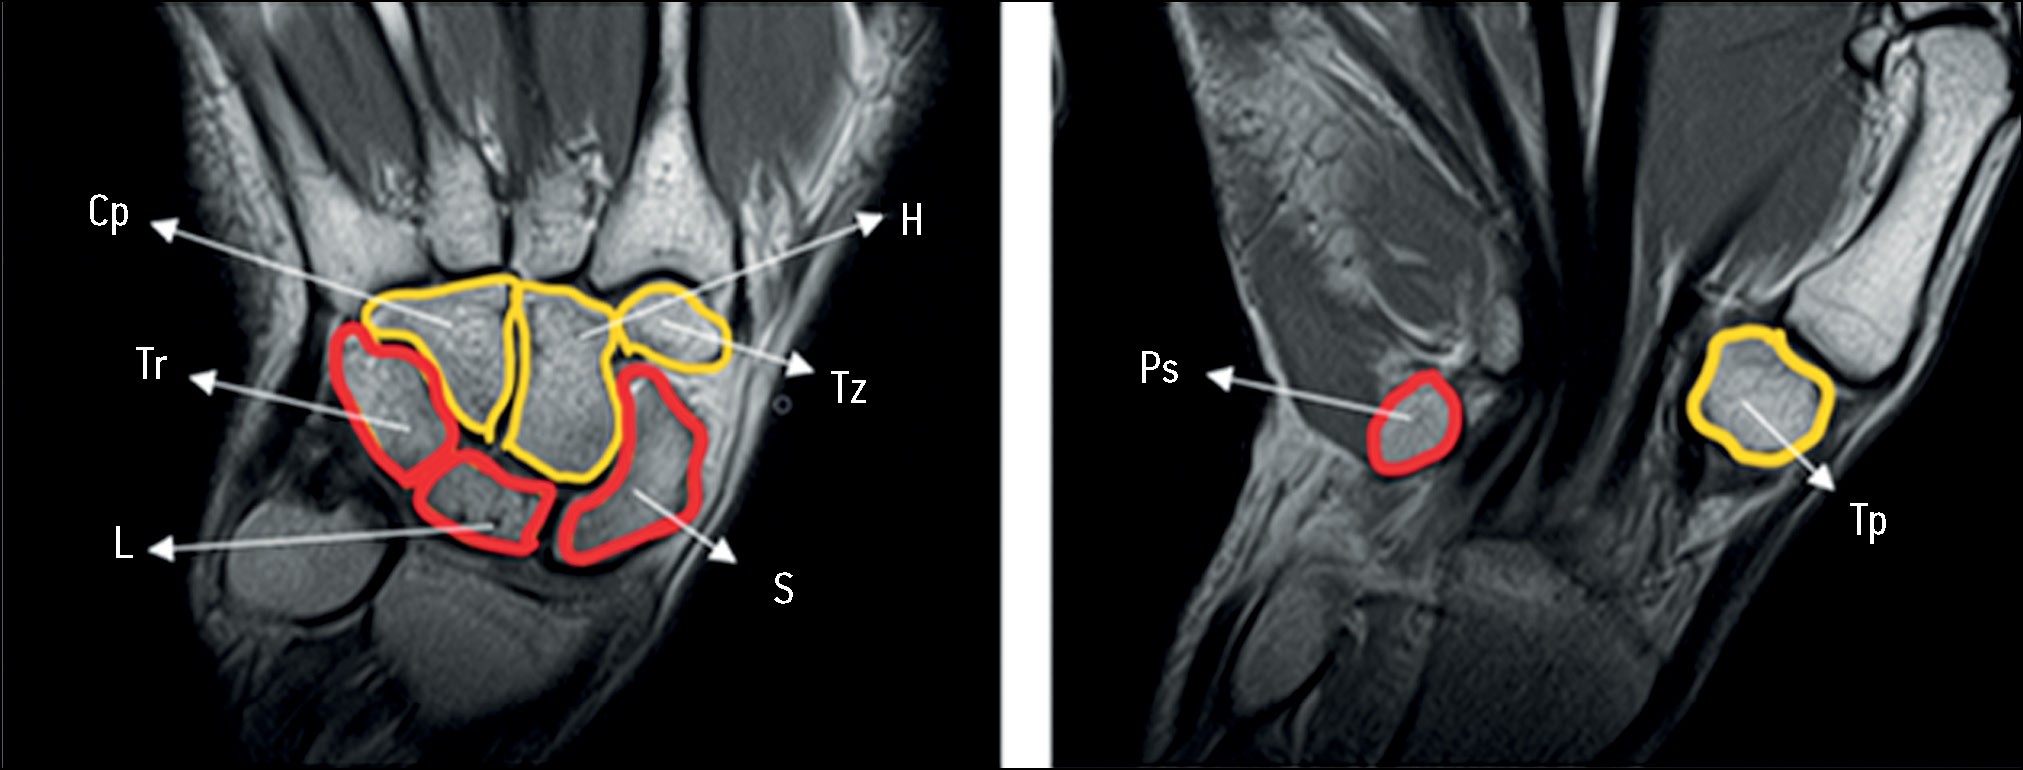

The hand is the distal part of the upper extremity, which includes the bones of the wrist, metacarpal bones, and phalanges, as well as ligaments, vessels, and nerves. The wrist consists of two rows of bones: the proximal row, consisting of the scaphoid (os scaphoideum), lunate (os lunatum), triquetrum (os triquetrum), and pisiform (os pisiforme) bones, and the distal row, consisting of the trapezium (os trapezium), trapezoid (os trapezoideum), capitate (os capitatum), and hamate (os hamatum) bones [11] (Fig. 7).

Fig. 7. Left hand, wrist bones, and magnetic resonance imaging (T1-weighted images, coronal plane). The proximal bone row is marked in red; the distal bone row is marked in yellow. S, scaphoid bone; L, lunate bone; Tr, triquetral bone; Ps, pisiform bone; Tp, trapezium bone; Tz, trapezoid bone; H, hamatum, Cp, capitate bone.